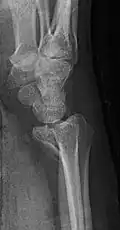

Radiografia projecional da fratura de Barton.